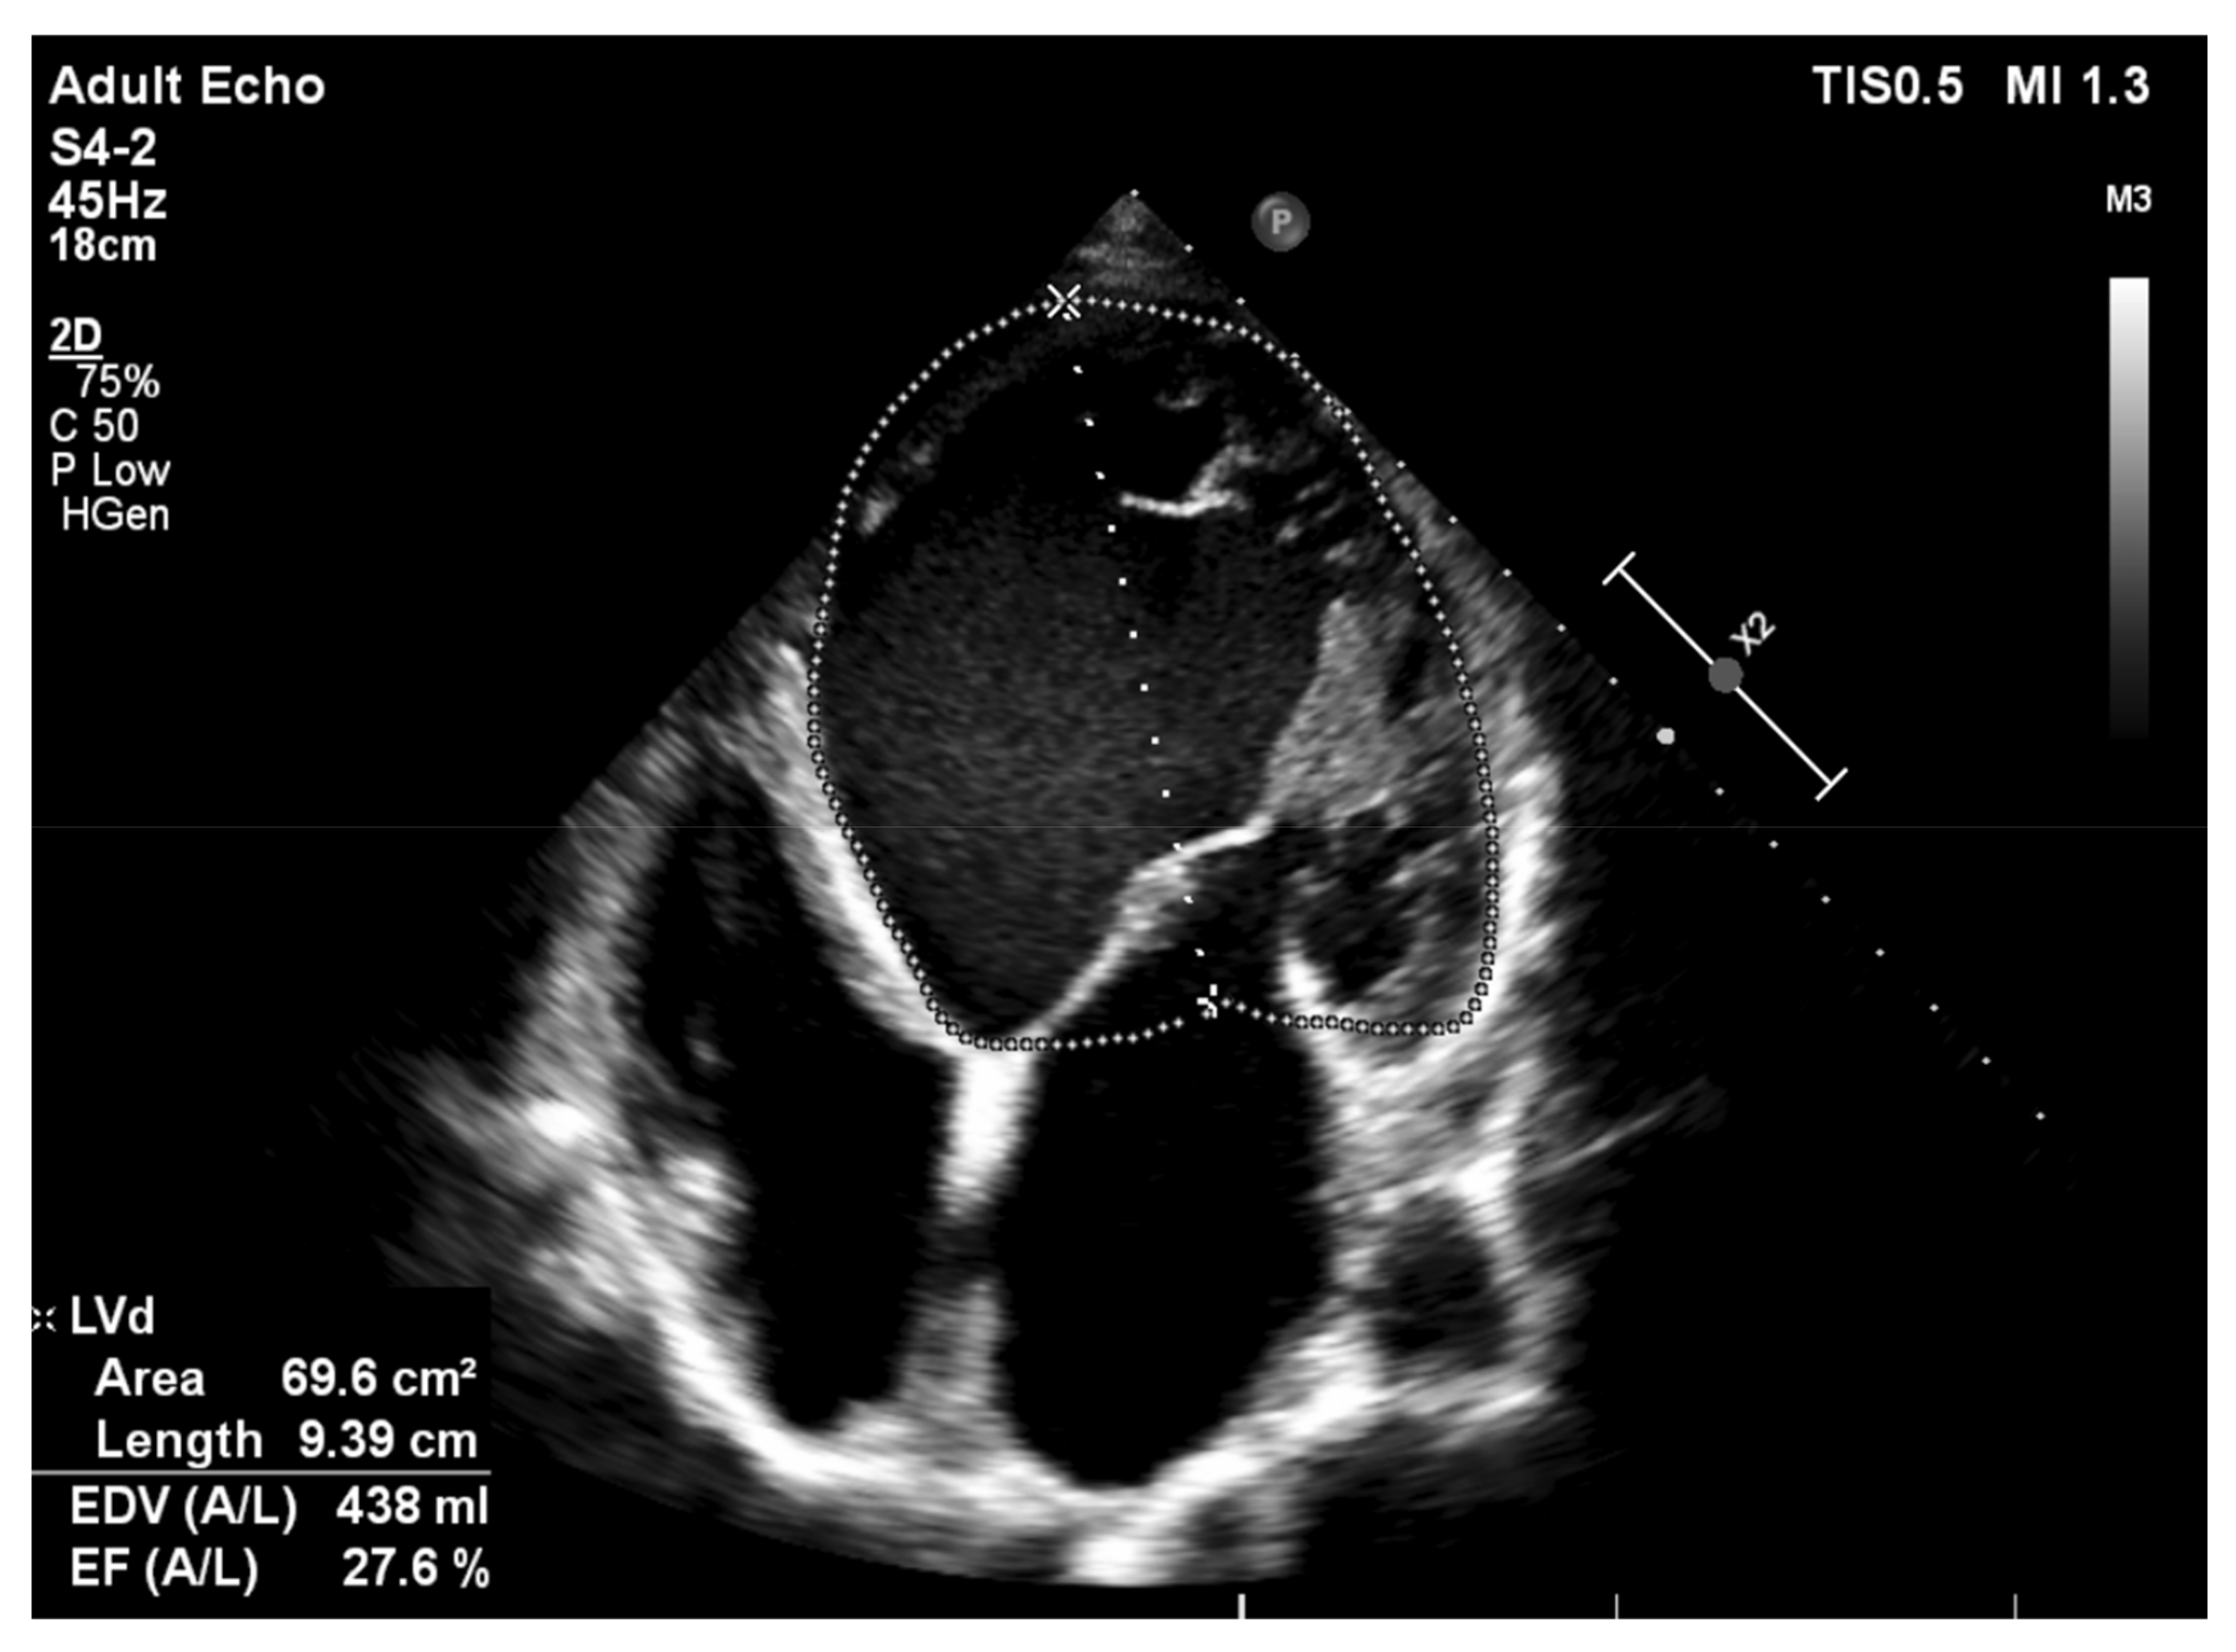

4. Alcoholic Cardiomyopathy